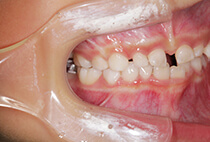

20代女性の患者さま。

八重歯の見た目が気になってご来院されましたが、実は顎の痛みや開口障害など、顎関節症の症状もありました。

そのため、かみ合わせと顎関節症の治療を同時に行ったにもかかわらず、2年間で治療が終了。

かみ合わせが整い咬筋の過緊張も改善しました。咬筋の肥大も治ってフェイスラインがすっきりしました。

最終的には美しい歯並びと、安定した痛みのないかみ合わせが実現しました。

八重歯が気になる

叢生、顎関節症、開口障害

20代女性

矯正治療2年

24回

唇側矯正

矯正:1,161,600円+毎月調整量:6,050円

しっかり前歯を下げるために、インプラントアンカーを使用してコントロールしました。

かみ合わせが整うと咬筋の過緊張が改善。

過緊張による筋肉肥大も改善しフェイスラインもすっきりしました。

治療前

治療後